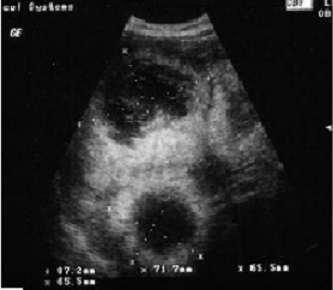

Image echographique de

metastase du foie : Aspect lesionaire est multiple

en nodulaire iso echogen avec contour

hypoechogen ( Bull's eye sign) |

Signe de "Bull

eye sign" des metastases du foie . Image

echographique du foie |